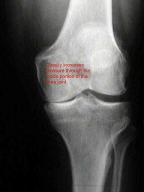

Knee Arthritis - VQ ActionCare

Knee Arthritis Rehabilitation Using the Resistance Chair General Information Osteoarthritis affecting the knee is a common and often painful condition commonly ... Access Full Source